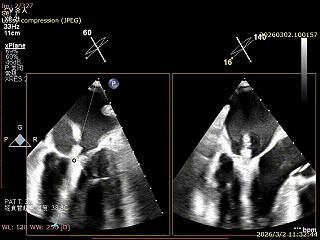

患者为房间隔缺损术后合并功能性二尖瓣反流(FMR),病变位于二尖瓣2区偏3区,因既往ASD修补史(可降解房间隔缺损封堵器),致房间隔穿刺区域存在瘢痕粘连、穿刺难度增加,于靠下靠后位置穿刺,避开房间隔缺损封堵伞,其余病变解剖结构相对简单;术前制定手术策略,拟使用1把XTR行二尖瓣修复,术中克服瘢痕粘连难点成功完成房间隔穿刺,穿刺点距二尖瓣瓣环平面3.1cm,将XTR‑CDS送入左心房,通过”A”旋钮旋转180度借高度,LVOT切面夹子严重Huge,使用”+”旋钮一键消除Huge,通过操控“M”旋钮将二尖瓣夹精准定位于2区正上方,完成弹道测试及Orientation调整后,于2区将夹子送入左心室,顺利捕捞并夹持瓣叶后缓慢闭合夹臂;TEE检查示二尖瓣反流充分降低至微量,二尖瓣双孔组织桥稳定,跨瓣压差2mmHg,肺静脉逆流明显改善,手术安全顺利结束。

穿刺可用高度不足,通过”A”旋钮旋转180度借高度,此时LVOT切面夹子严重Huge

使用”+”旋钮一键消除Huge